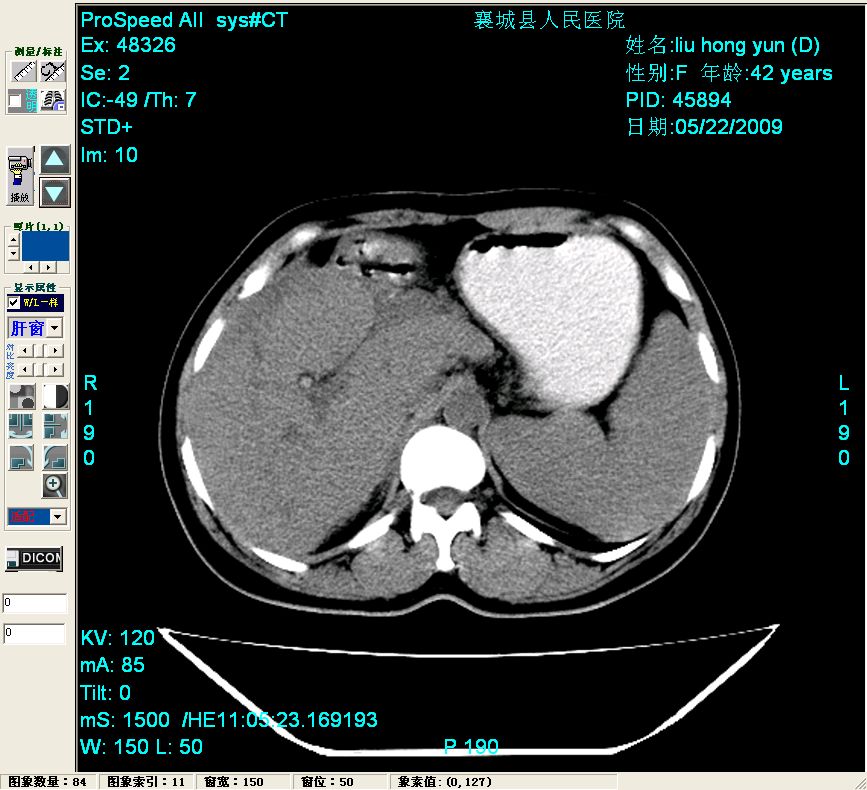

平扫:

平扫左肝外叶体积显著减小,左肝外叶见多房囊性低密度区,左肝实质及右肝前叶浅表实质呈低密度改变,左肝及右肝前叶胆管扩张,脾大

胰头部见结节状高密度影,其前方略可分辨扩强胆部管,平扫到增强始终有,但现在尚难与胃肠造影剂鉴别.

结合病史考虑,1现在引起黄疸体征的原因应该是胆总管胰段结石阻塞,建议局部胃肠造影剂排空后复查.

2左肝及右肝前叶表现考虑胆囊摘除术后所致的肝动门脉瘘形成,慢性纤维组织炎性增生.不完全除外左肝胆管细胞癌

3脾大,可能与动门脉瘘所致门脉高压有关